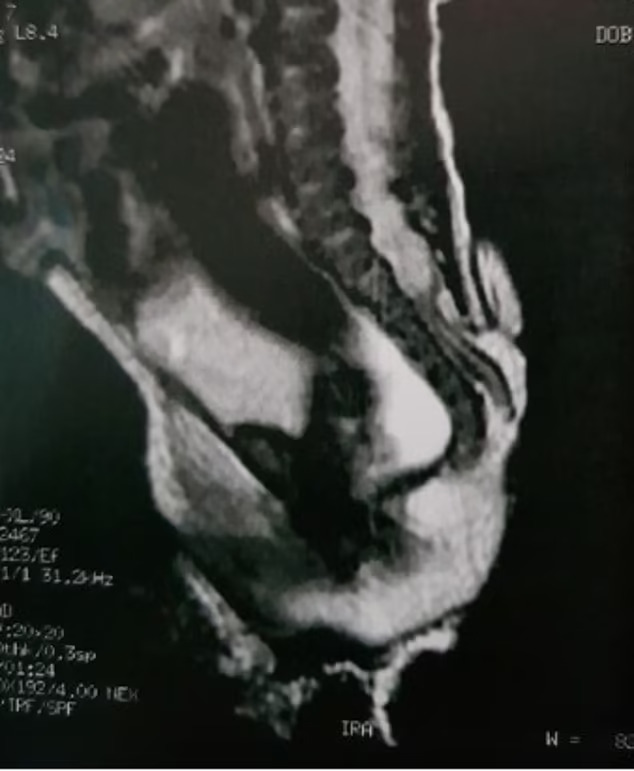

Девојчето е родено со спина бифида, редок дефект на ‘рбетот кој се јавува во утробата – предизвикувајќи празнина во’ рбетот. Според лекарите кои го лекувале девојчето, најверојатно тоа е причината поради која имала опашка. Операцијата, исто така, ја затвори дупката, како ѝ ја ослободи од израстокот.

Лекарите рекоа дека опашката никнала од лумбосакралниот регион – областа што го поврзува ‘рбетот со карлицата. Лекарите го дијагностицирале додатокот како „човечка псевдоопашка“.